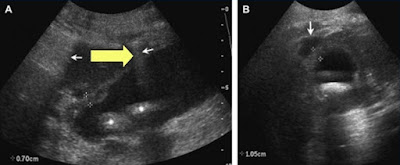

A. Ultrasound images of gall stone sitting position

B: Decubitus position